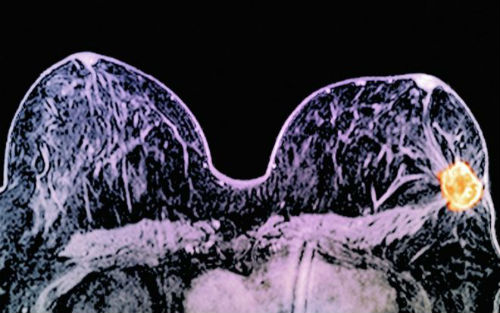

研究人员给予肿瘤大小在1-3厘米的患者施以这种药物组合治疗,在不到两个星期的时间内,11%的患者肿瘤完全消失,17%的患者肿瘤缩小了5毫米。目前HER2阳性乳腺癌都是接受手术治疗,随后进行化疗和赫赛汀治疗。